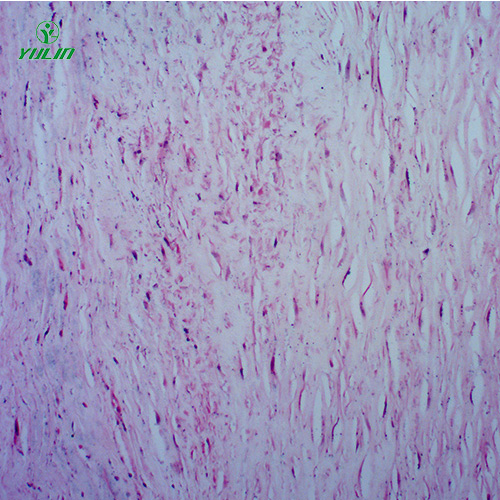

湖南炎症病理玻片

产品内容说明 /Product description

人体病理切片,炎症病理玻片,炎症病理玻片价格